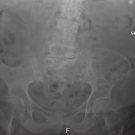

A 60-year-old man presented to the emergency department with abdominal pain, mild rectal bleeding, tenesmus, and frequent liquid mucous stools for 18 days, reporting “loose stools” in the morning and...